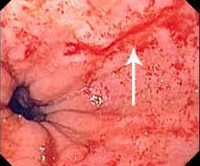

Диагностика синдрома Мэллори-Вейса основывается на эндоскопических данных. Эндоскопия пищеварительного тракта — основной и самый информативный метод исследования, позволяющий увидеть линию разрыва пищеварительного тракта, определить характер поражения, поставить диагноз и начать лечение.

При синдроме Мэллори-Вейса обнаруживают линейную трещину слизистой оболочки верхней части желудка. Обычно у больных определяется один разрыв. В крайне редких случаях их может быть 2 и более. Очаг поражения имеет длину около 3 см и расстояние между краями трещины – несколько мм. Если во время фиброгастроскопии обнаруживают кровоточащий сосуд, кровотечение сразу же останавливают.

примеры эндоскопии синдрома Мэллори-Вейса

- Эзофагогастроскопия. Введение гибкого эндоскопа через ротовую полость позволяет оценить состояние эпителиальной оболочки верхних отделов ЖКТ и обнаружить линейные разрывы, которые обычно локализованы в области перехода пищевода в желудок. С помощью визуального осмотра удается установить глубину поражения стенки пищевода или желудка.